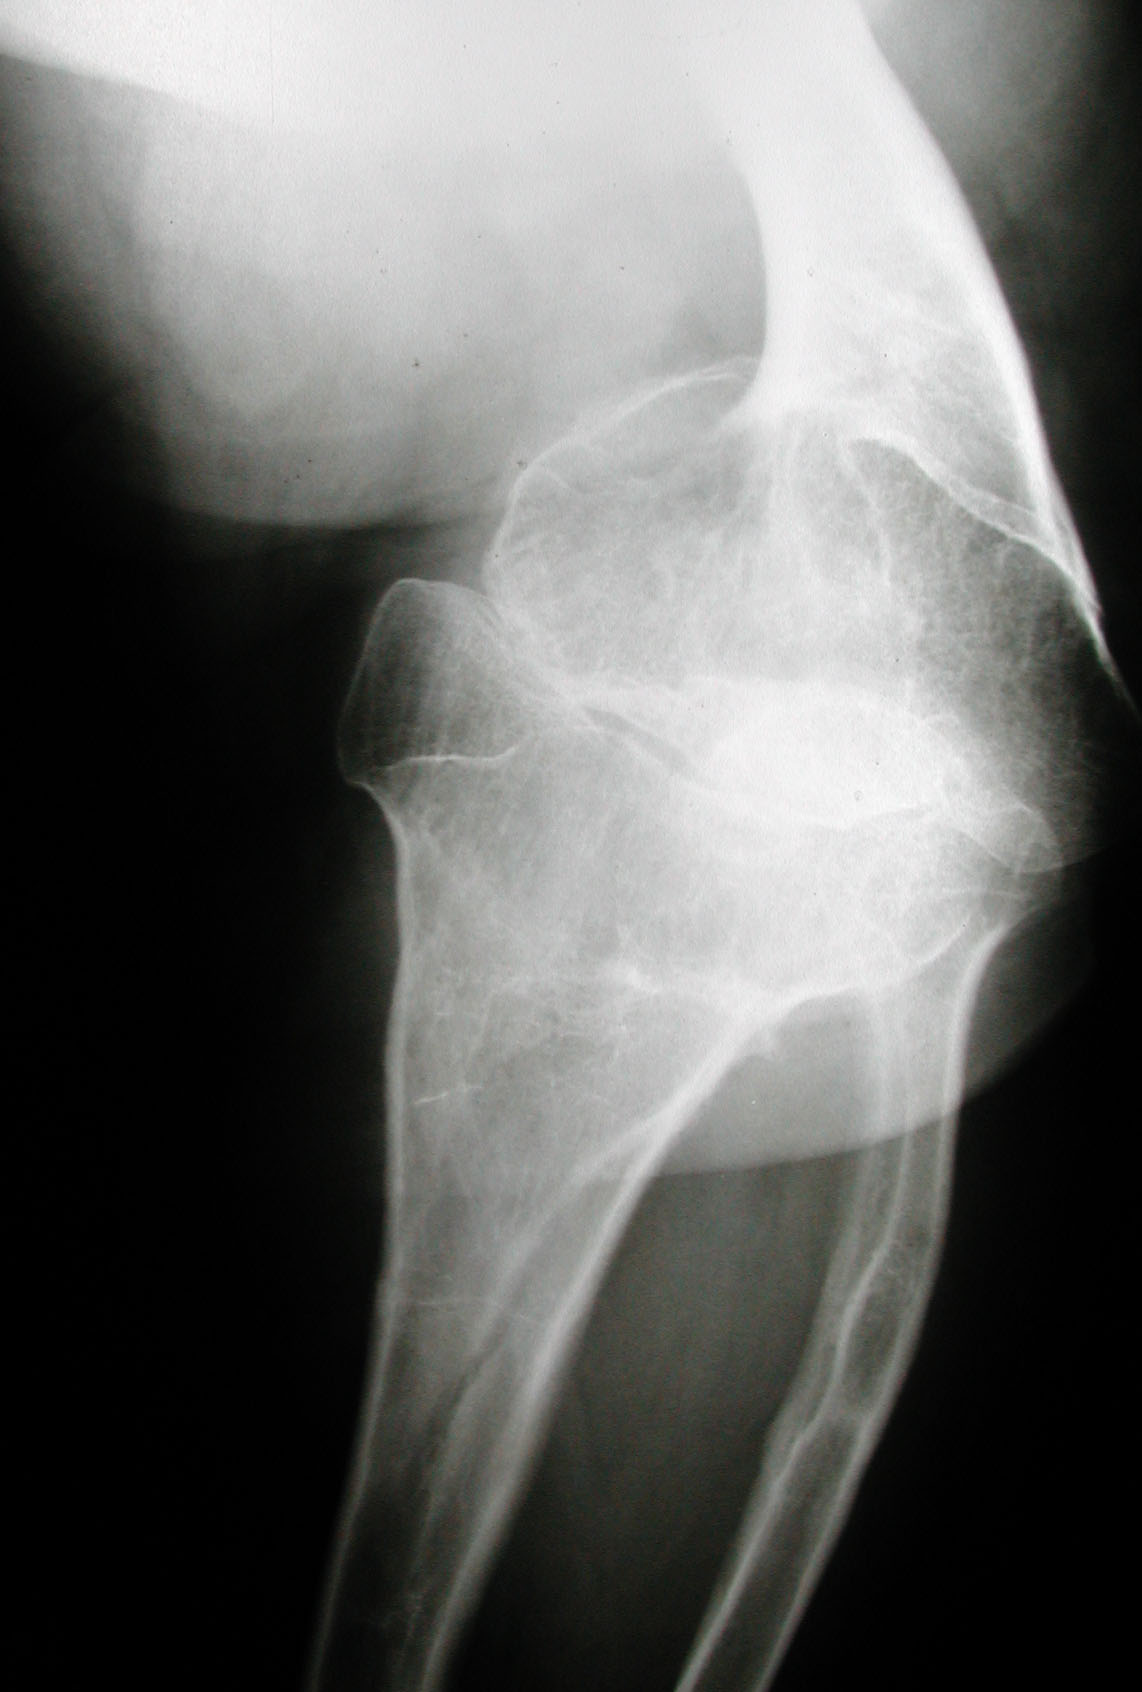

Seudoacondroplasia. [Pseudoachondroplasia]